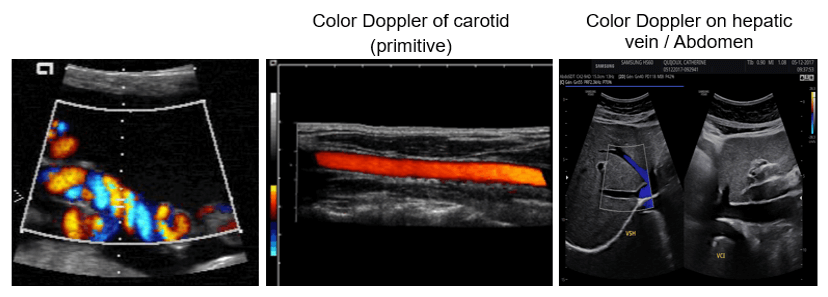

In other words, the color Doppler technique estimates the average velocity of flow within a vessel by color-coding the information. The direction of blood flow is assigned by the color red or blue, indicating flow toward or away from the ultrasound transducer, and is superimposed on B mode data from stationary structures within the beamwidth. By convention, blood flow traveling toward the transducer is encoded in red, and blood flow moving away from the transducer is encoded in blue.

Examples of Images

Color Doppler is mostly used in fetal and hepatic ultrasound, where the primitive carotid and the hepatic vein are well visible.